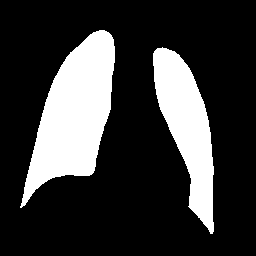

Research is based on the second update of the "COVID-19 Radiography Database" Chowdhury et al. (2020); Rahman et al. (2021); Cov (2022) developed by a team of researchers from Qatar University, Doha, Qatar, and the University of Dhaka, Bangladesh along with their collaborators from Pakistan and Malaysia in collaboration with medical doctors. The database incorporates posterior-to-anterior (AP)/anterior-to-posterior (PA) chest X-ray images from multiple public sources Vayá et al. (2020); Winther et al. (2020); SIR (2020); Cohen et al. (2020a, b); Haghanifar et al. (2022); RSN (2018); Kermany et al. (2018) and contains: 3616 images of COVID-19-positive cases, 6012 images of lung opacity (non-COVID lung infection), 1345 images of viral pneumonia, 10192 images of healthy lungs. Images are provided after conversion to common PNG format with 256x256 dimensions. For each image, the dataset authors provided a corresponding lung segmentation mask obtained using a dedicated U-Net model Rahman et al. (2021). Sample images from the database are presented in Fig. 2.

Images in the original dataset are not framed consistently, with body parts visible in the image tending to differ depending on the original source. In order to remove this possible bias all images are cropped to a rectangular region of interest encompassing the corresponding lung mask. After cropping the images are resized to a common size of 128x128 pixels. An example of cropped and rescaled image is presented in Figs. 2f and 2g. Finally, the pixel values are normalised to [0; 1] scale. All images are grayscale with three channels present, such format is retained as an input for the classification networks as this is the format they were trained on originally. For the GAN training, a single-channel grayscale format is used which leads to faster execution.